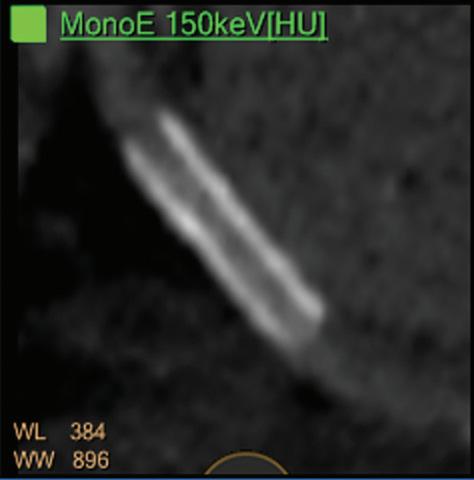

Once the pair (αp, αc) is calculated for every voxel, and since fp(E) and fc(E) are known functions of energy, one may synthesize monochromatic images at different energies. These images can be used for routine diagnosis similar to conventional images. With a single scan at 120 kVp (or 140 kVp for obese patients), a dual-layer spectral CT acquisition allows the reconstruction of virtual monochromatic images from 40 keV up to 200 keV, in increments of 1 keV. The minimum of 40 keV was chosen in order to stay above the k-edge of the most common materials including iodine (iodine k-edge = 33 keV). If the scan is performed at 120 kVp, the conventional CT images of a typical-size patient will display an attenuation corresponding to the average of the X-ray spectrum (˜70 keV in a body scan) but with beam hardening artifacts from dense structures (like bones) which are due to the polychromatic nature of the X-ray beam. Since the photoelectric effect is dominant at lower keV, and is relatively high for high Z materials, low keV imaging (below 70 keV for body) can be used to enhance the absorption of high Z material such as iodine (Z=53), compared to the conventional CT images.15,16 This can be of particular interest to enhance the iodine uptake for patients with renal dysfunction, where the total injected volume of iodinated contrast medium is very limited. This attenuation boost can also be very useful in the case of a missed injection (Figure 2a and b). Compton scattering on the other hand is dominant at higher keVs and does not exhibit a strong relationship with Z. High keV imaging will then be of particular interest to minimize the absorption of high Z materials and minimize all types of associated artifacts (metal beam hardening from metal implants, beam hardening from dense contrast medium, blooming of stents or calcium, etc.) (Figure 2c).17,18,19

18. Hickethier T., Baeßler B., Kroeger J.R., Doerner J., Pahn G., Maintz D., Michels G., Bunck A.C.; Monoenergetic reconstructions for imaging of coronary artery stents using spectral detector CT: In-vitro experience and comparison to conventional images; J Cardiovasc Comput Tomogr. 2017 Jan - Feb;11(1):33-39. doi: 10.1016/j.jcct.2016.12.005.